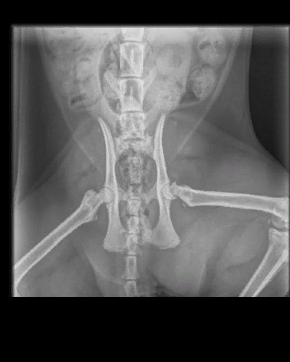

Однако в этот момент на руках у хозяйки пострадавшего четвероногого уже было заключение и рентгеновский снимок, на котором чёрным по белому написано, что у кота перелом.

Врач из ветклиники «Вет ZOO Доктор» — пишет, что у животного был выявлен «эпифизеолиз головки бедренной кости», что означает, что у животного присутствовала аномалия развитии. Однако на заключении, которое выдали женщинам после рентгена и проведённой операции, нет ни слова про «врождённую аномалию». В выписке из медицинской карты животного говорится, что у кота был диагностирован перелом головки бедренной кости и проведена операция по её удалению.